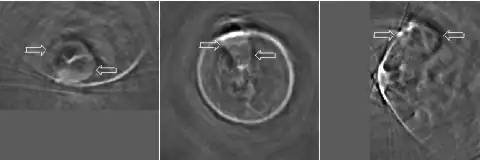

Thermoacoustic imaging was originally proposed by Theodore Bowen in 1981 as a strategy for studying the absorption properties of human tissue using virtually any kind of electromagnetic radiation.[1] But Alexander Graham Bell first reported the physical principle upon which thermoacoustic imaging is based a century earlier.[2] He observed that audible sound could be created by illuminating an intermittent beam of sunlight onto a rubber sheet. Shortly after Bowen's work was published, other researchers proposed methodology for thermoacoustic imaging using microwaves.[3] In 1994 researchers used an infrared laser to produce the first thermoacoustic images of near-infrared optical absorption in a tissue-mimicking phantom, albeit in two dimensions (2D).[4] In 1995 other researchers formulated a general reconstruction algorithm by which 2D thermoacoustic images could be computed from their "projections," i.e. thermoacoustic computed tomography (TCT).[5] By 1998 researchers at Indiana University Medical Center[6] extended TCT to 3D and employed pulsed microwaves to produce the first fully three-dimensional (3D) thermoacoustic images of biologic tissue [an excised lamb kidney (Fig. 1)].[7] The following year they created the first fully 3D thermoacoustic images of cancer in the human breast, again using pulsed microwaves (Fig. 2).[8] Since that time, thermoacoustic imaging has gained widespread popularity in research institutions worldwide.[9][10][11][12][13][14][15] As of 2008, three companies were developing commercial thermoacoustic imaging systems – Seno Medical,[16] Endra, Inc.[17] and OptoSonics, Inc.[18]

Microwaves have also been used to form 3D thermoacoustic images of the human breast. One of the first devices to do so is depicted in Fig. 10. It consisted of an array of eight waveguides, which directed microwave energy into the breast. A transducer array was rotated in synchrony with the waveguides in order to acquire sufficient data to reconstruct the internal structures of the breast. Figure 11 shows an animation of the typical glandular tissue pattern in a normal breast.